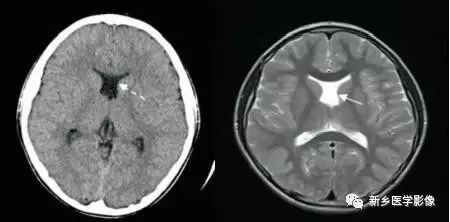

❶ 导水管狭窄

中脑导水管是脑室系统最狭窄的通道,也是脑脊液循环受阻最常见的部位。

导水管粘连主要见一于颅内感染和出血后,可于胚胎期发生,也可见于出生后任何年龄。导水管粘连所致狭窄多位于导水管远端。狭窄段长度通常为2一5mm,狭窄近端异水管可呈喇叭口样扩张。

导水管狭窄时,三脑室扩大常很显著,三脑室前部视隐窝和漏斗隐窝扩张或消失,三脑室后部松果体隐窝和松果体上隐窝明显后突,向小脑上池疝入。严重者可压迫小脑。